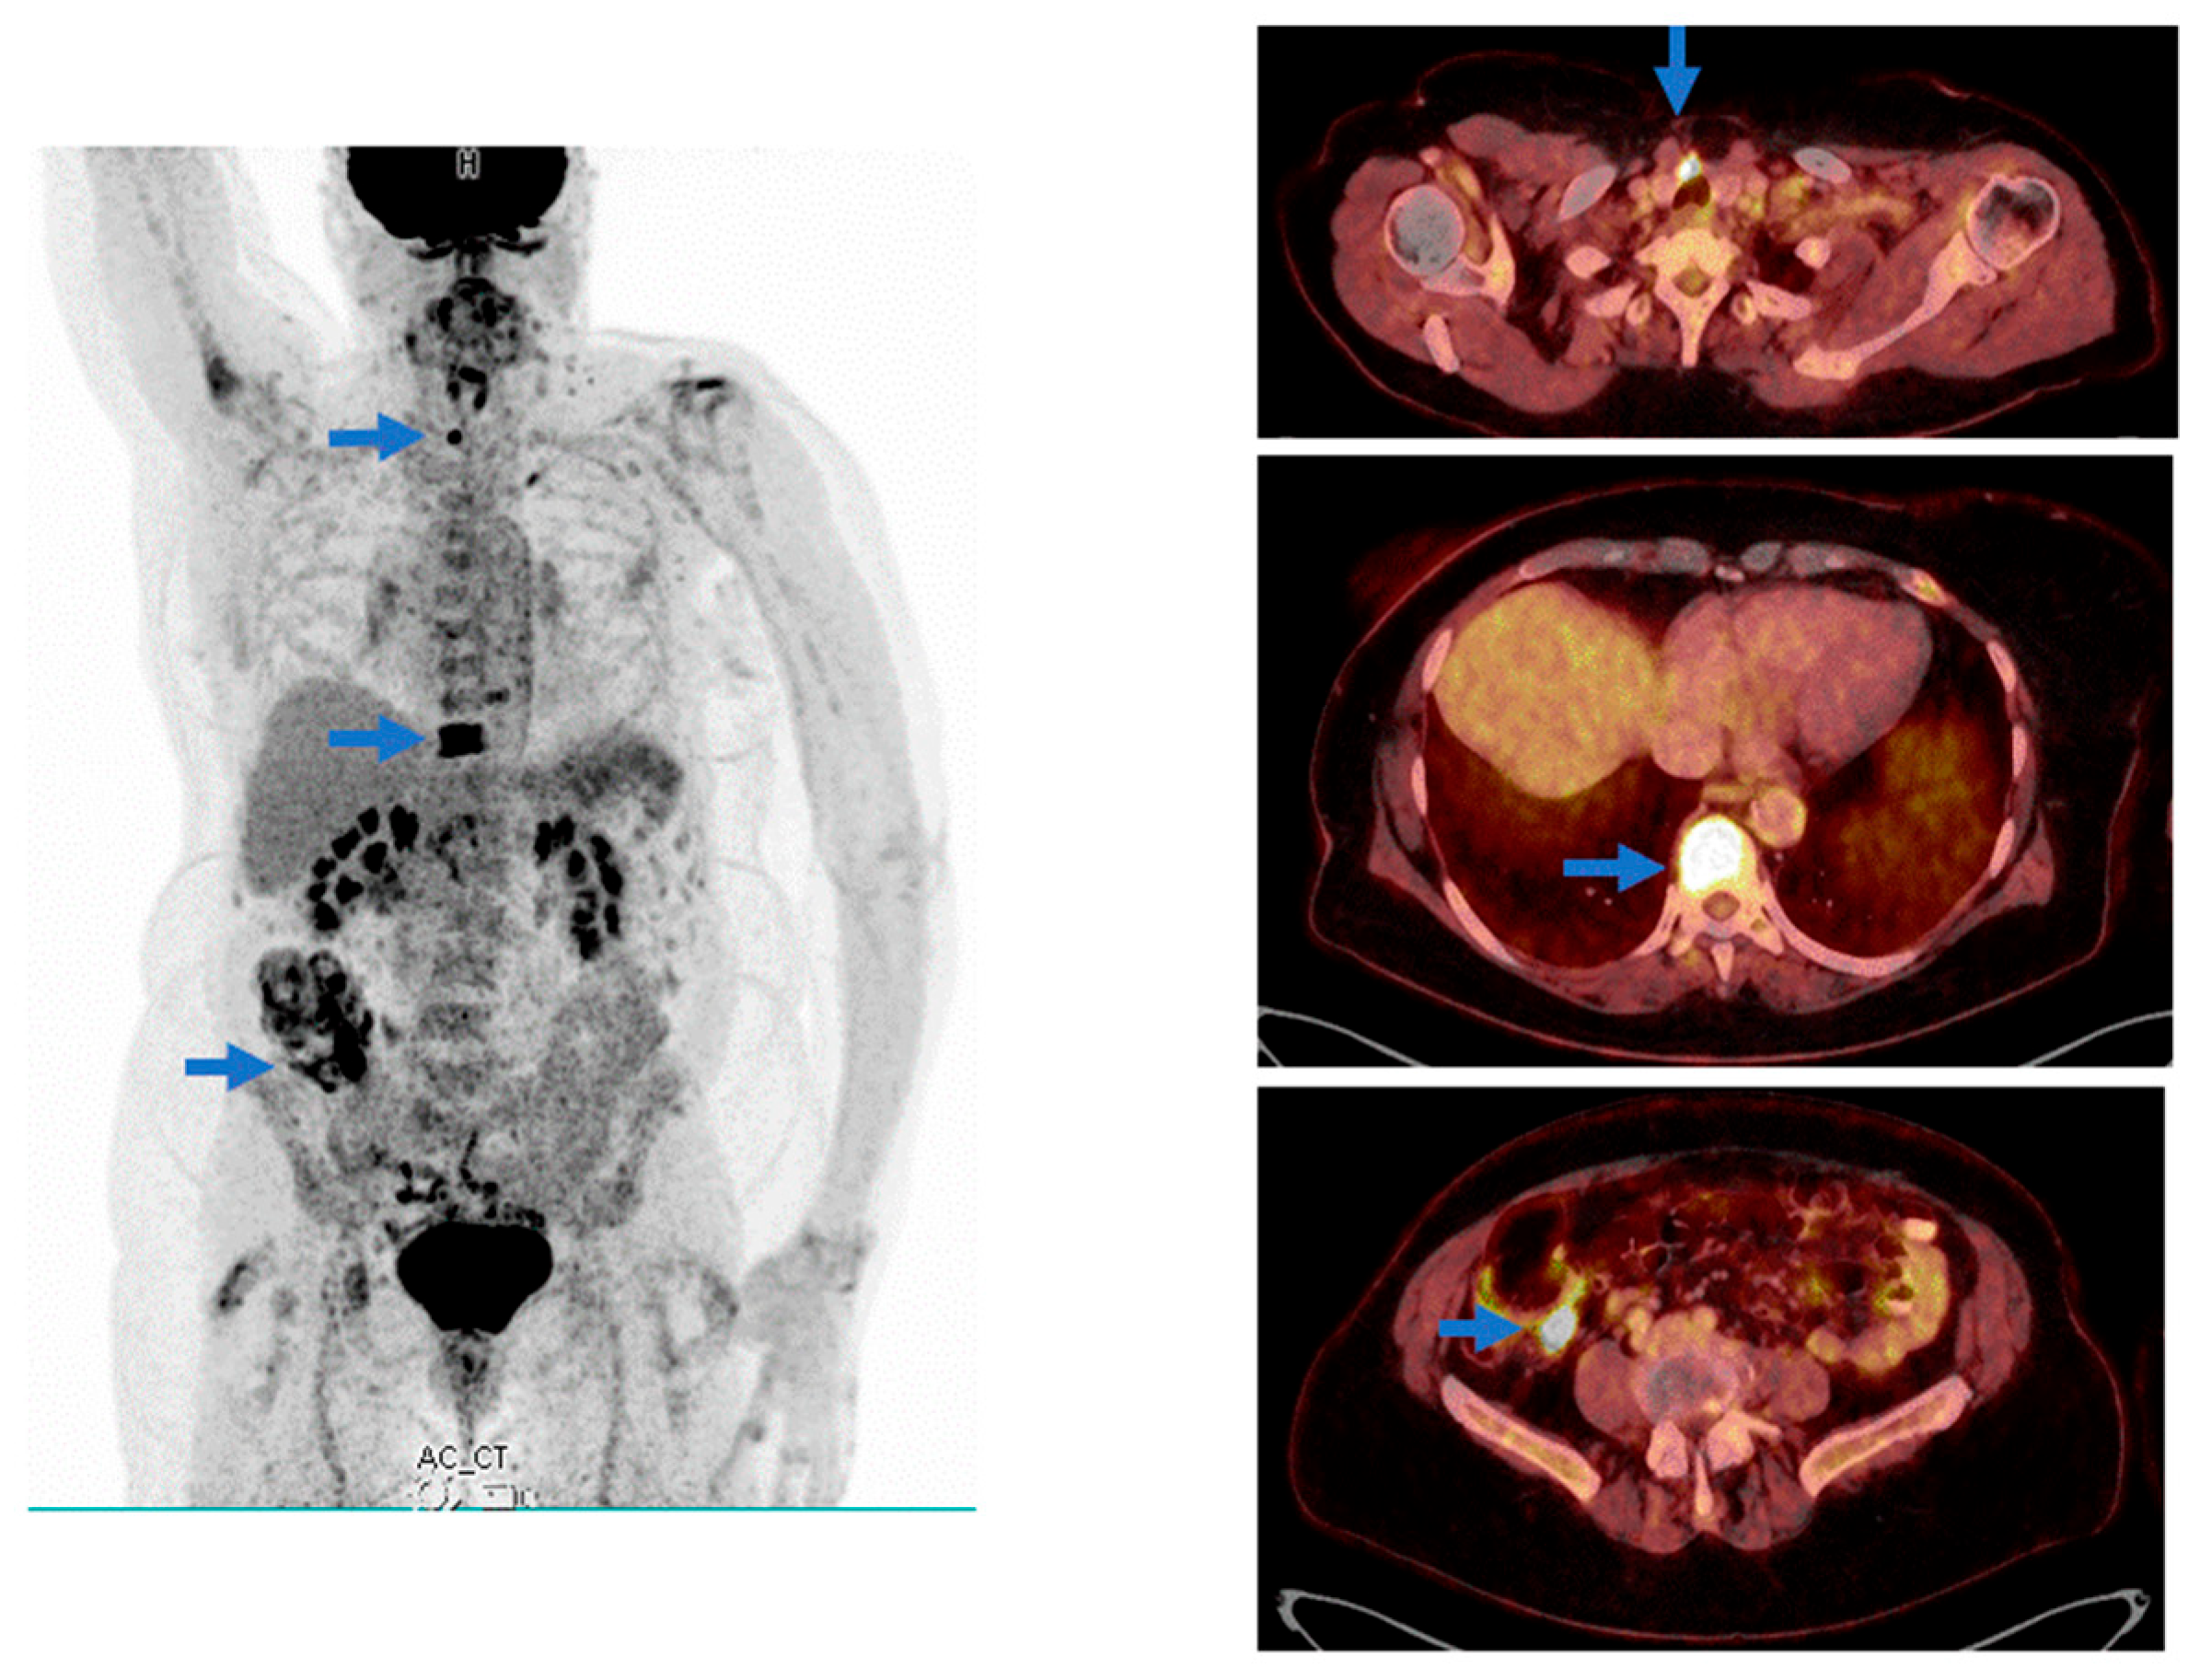

Mild SARS-CoV-2 Infection with the Omicron Variant Mimicking Metastatic Cancer on Whole-Body 18-F FDG PET/CT Imaging

2. Case Presentation